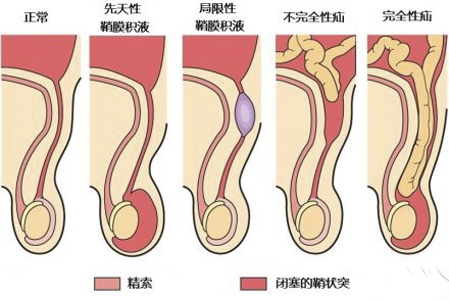

A:鞘膜積液手術恢復起來相對來說比較快,術後待傷口癒合,通常大概需要一週左右的時間即可恢復正常,但是需要注意避免過度劇烈的運動,以及避免傷口感染。對於鞘膜積液,通常比較常見的有睪丸鞘膜積液、精索鞘膜積液、混合型鞘膜積液、交通鞘膜積液、嬰兒型鞘……

A:對於一歲半的鞘膜積液,要明確診斷是哪種類型的鞘膜積液,是否可以自愈需要根據情況判斷,說明如下:1、單純性鞘膜積液:可以先觀察隨訪,不做處理,因為兩歲以下的兒童鞘膜積液多可自行吸收,嬰幼兒的鞘膜積液禁忌抽吸;2、交通性鞘膜積液:則考慮要進……

A:成人的鞘膜積液通常不能自愈,對於較大的鞘膜積液,必要時需進行手術相關的治療。鞘膜積液相對來說原因比較複雜,而且種類也比較多,包括交通性的鞘膜積液,或者睪丸鞘膜積液、精索鞘膜積液等,通常對於嬰幼兒的鞘膜積液,隨著年齡增加可以自行消失,而對於成……

A:精索鞘膜積液屬於泌尿男生殖系統疾病,應當在泌尿外科就診。精索鞘膜積液屬於鞘膜積液的一種,其他類型還包括睪丸鞘膜積液、混合性鞘膜積液、交通性鞘膜積液以及嬰兒型鞘膜積液。臨床表現多數無自覺症狀,多於體檢時偶然發現。隨著囊腫增大、張力增高,可以有……

A:正常情況下睪丸鞘膜腔內是可以有一些液體的,保證睪丸在陰囊內具有一定的活動範圍,隨著睪丸陰囊鞘膜腔的液體增加,我們稱之為鞘膜積液。鞘膜積液可以分成睪丸鞘膜積液、精索鞘膜積液或者混合型的鞘膜積液,以及交通性鞘膜積液和嬰幼兒的鞘膜積液,鞘膜積液在……

A:精索鞘膜積液多半為先天形成,要了解其形成的原因先要了解部分解剖。睪丸在胎兒時期位於腹腔內,在出生前後部分腹膜,隨著睪丸沿著腹股溝管下降,直降到陰囊當中,形成睪丸的固有鞘膜,沿途鞘膜逐漸就會閉鎖形成纖維索條。如果出生以後部分閉鎖不全,就會在各……